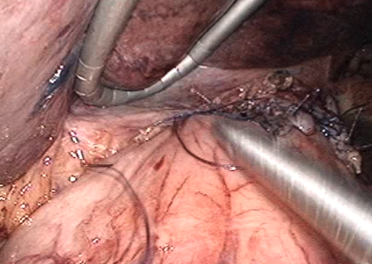

実際の腹腔鏡による胃切除術の一部をお見せします。胃を切るだけでなく、胃に行く血管の周りについたリンパ節をしっかりとる事が重要です。

まず、胃に付着する“エプロン”のような脂肪の膜を切り開き、胃や胃に行く血管を切る準備をします。

この時にこのエプロンに入り込んでくる血管も切り離します。脾臓に行く血管から出る胃の血管を、脾臓の近くで切り離します。 - 2